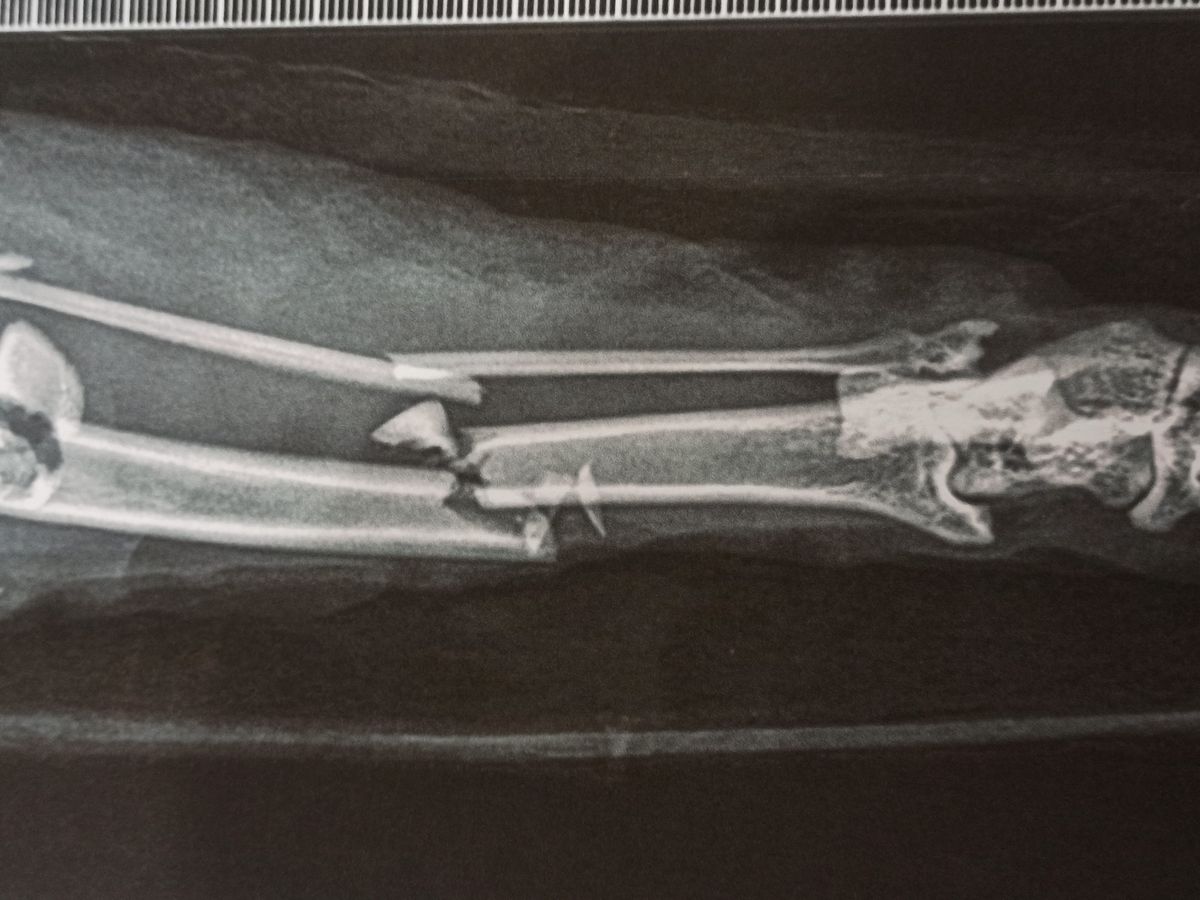

Scarlett ha avuto un brutto incidente, ha bisogno di un operazione e noi in questo momento non possiamo permetterci una spesa cosi alta.